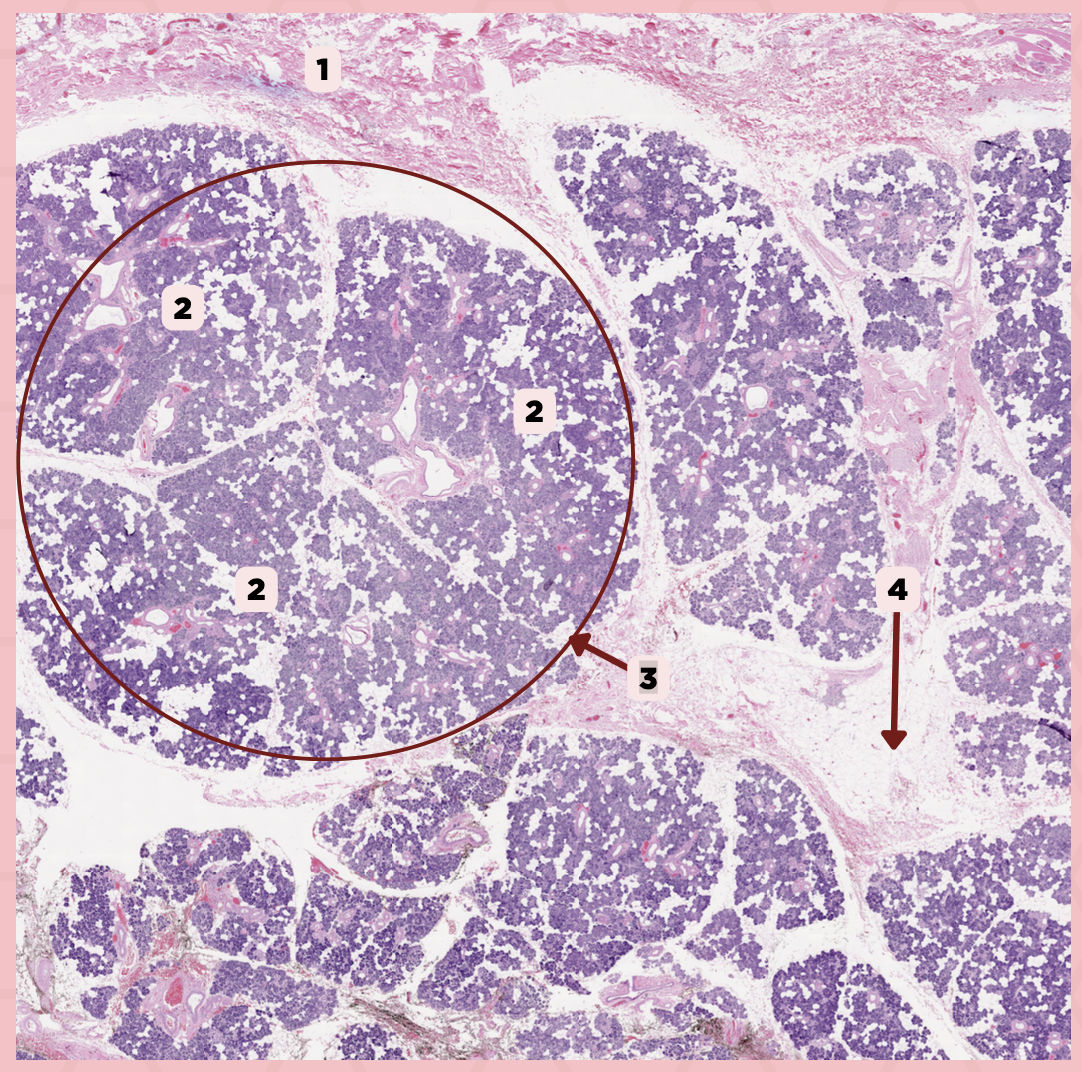

Parotid

Identify the specimen.

Capsule

Identify the structure labeled as 1.

Septa

Identify the structure labeled as 2.

Lobule

Identify the structure labeled as 3.

Lymph Node

Identify the structure labeled as 4.